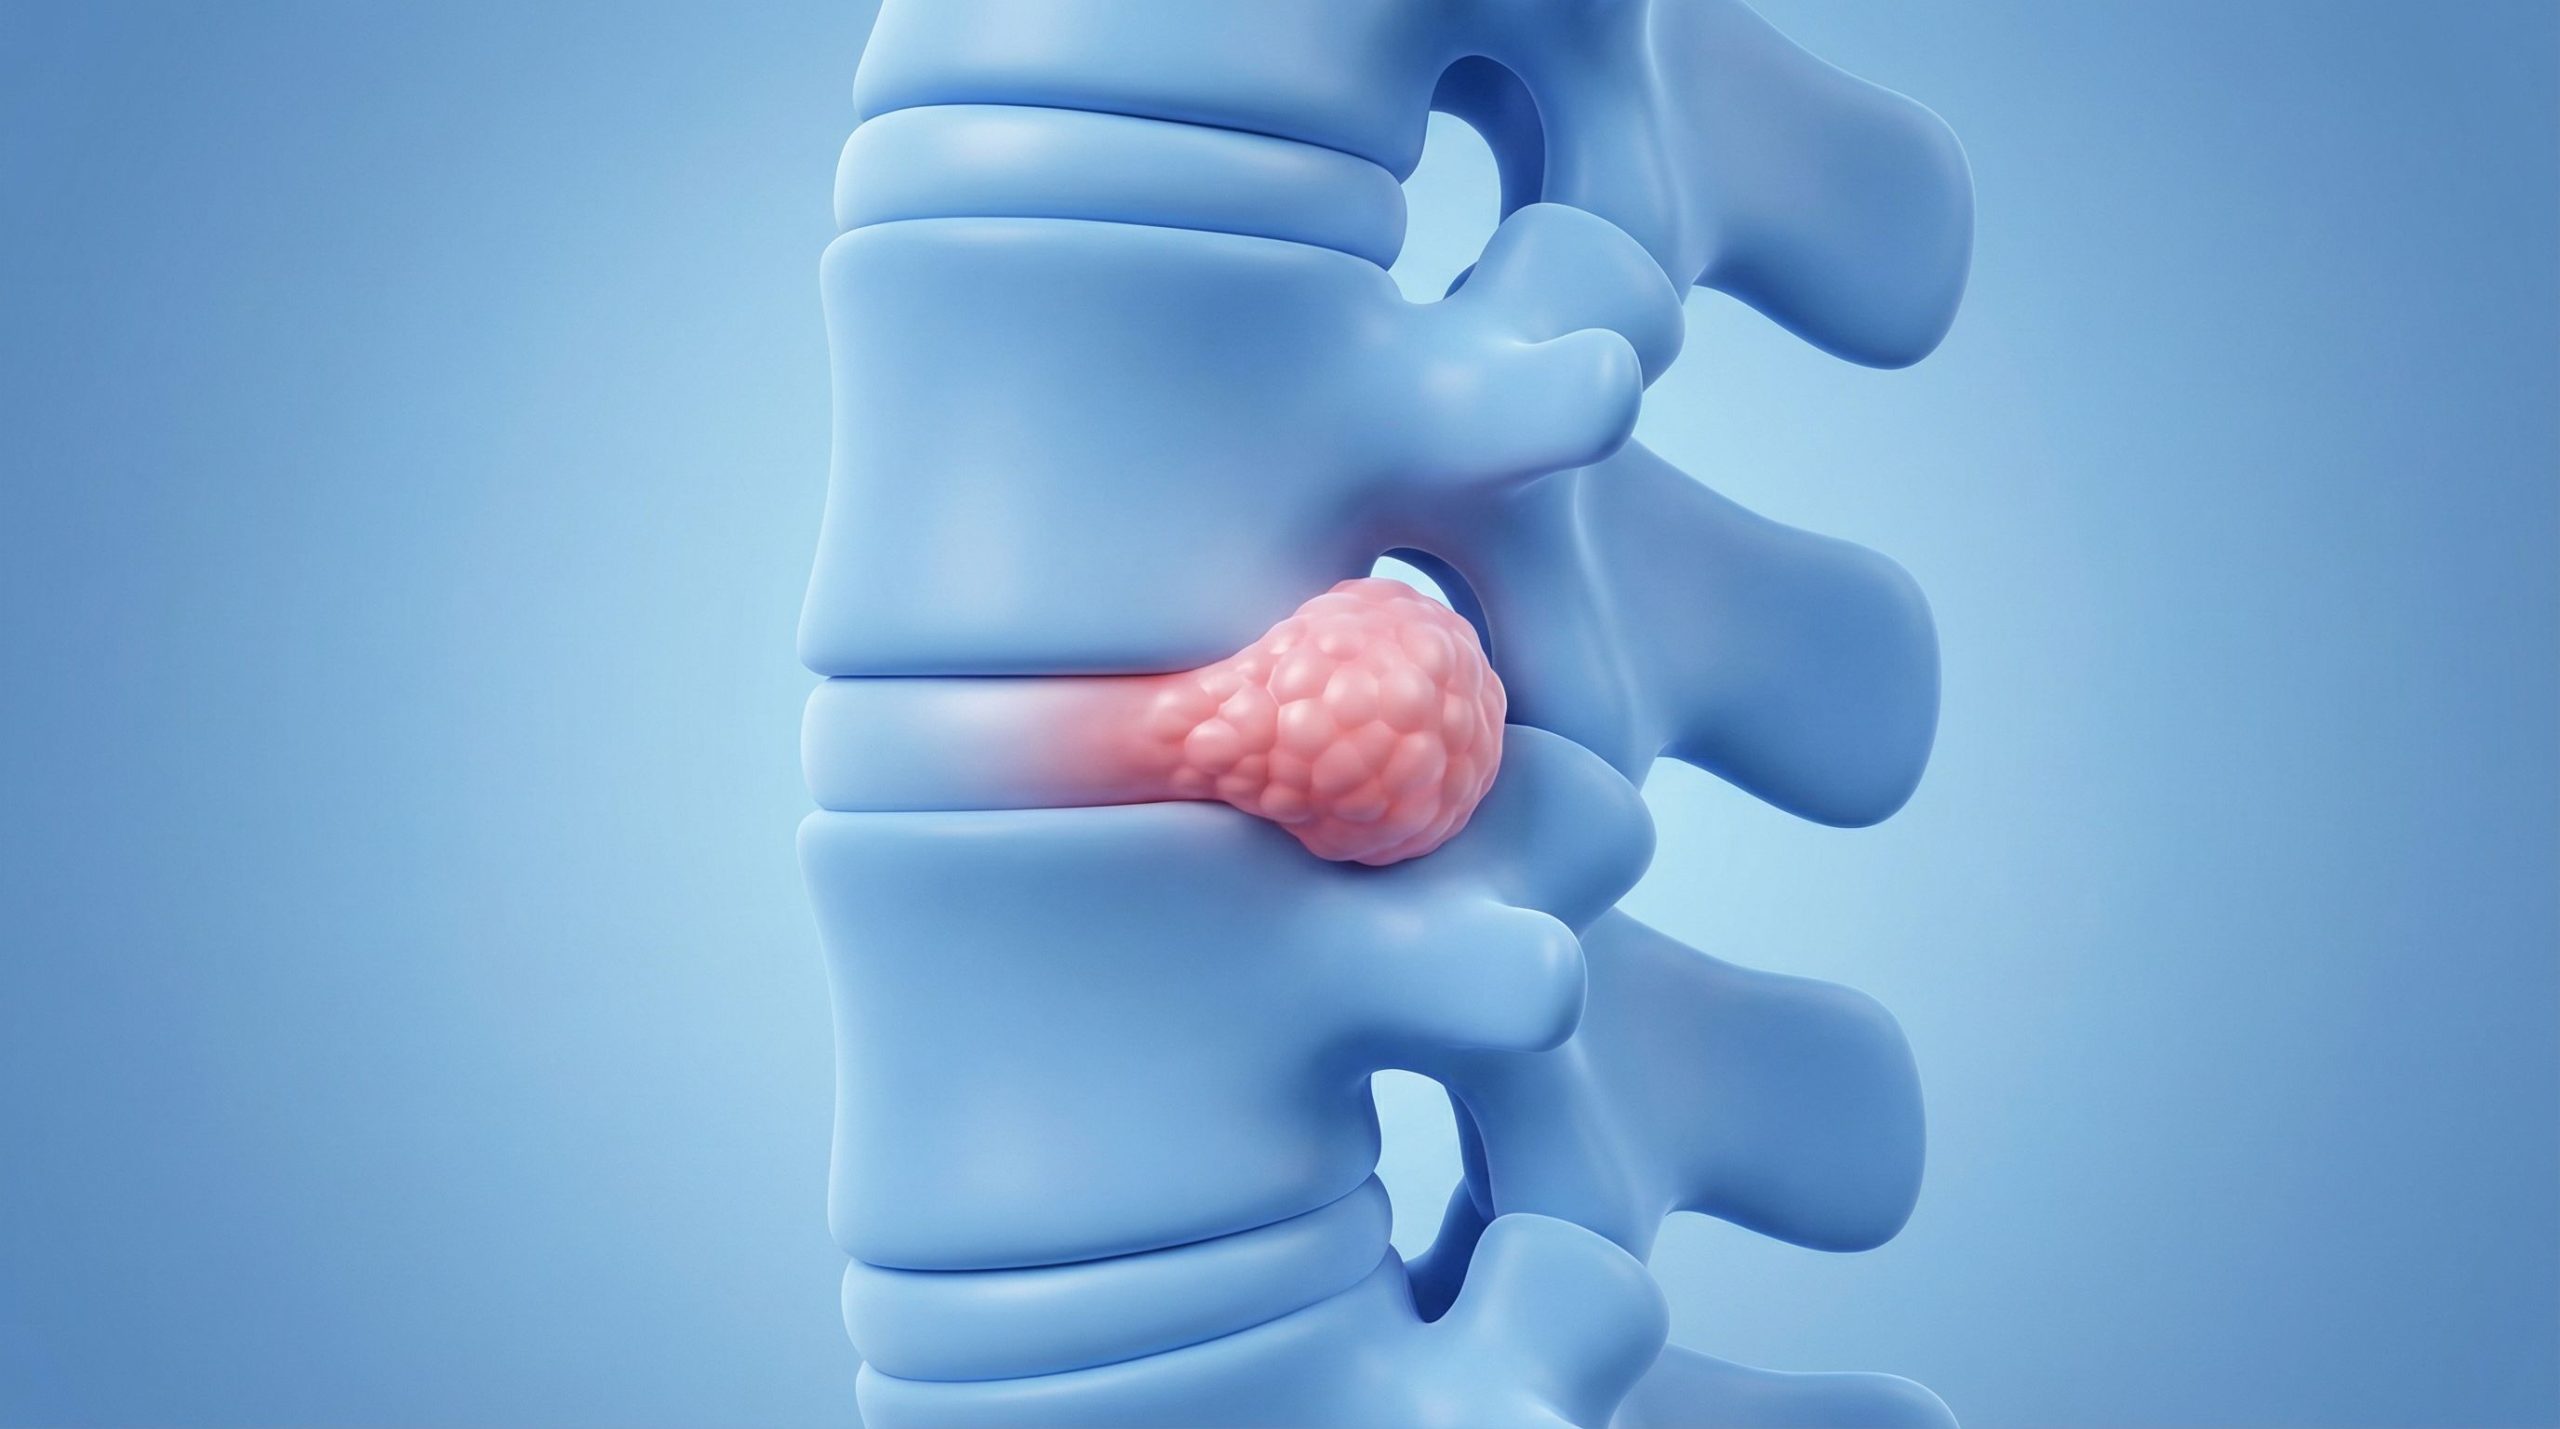

Imaginez un instant qu’on puisse réparer une colonne vertébrale fragilisée avec… de la graisse. Ça semble un peu fou, non ? Pourtant, c’est la piste très sérieuse qu’explore une équipe de chercheurs de l’Université métropolitaine d’Osaka. Une récente étude sur des rats a montré que les cellules souches provenant de nos tissus adipeux, notre graisse corporelle quoi, ont une capacité assez incroyable à guérir les fractures des vertèbres et à redonner de la force aux os. Cette découverte pourrait bien ouvrir la porte à des traitements beaucoup moins lourds et plus sûrs pour des maladies comme l’ostéoporose.

Parmi toutes les fractures possibles, celles qui touchent la colonne vertébrale, les fameuses fractures par compression, sont les plus fréquentes. Et elles ne sont pas anodines. Loin de là. Elles entraînent souvent une perte d’autonomie, nécessitent des soins de longue durée et, il faut bien le dire, elles peuvent gâcher la vie. Trouver de meilleurs traitements n’est donc pas un luxe, c’est une urgence absolue.

C’est là que les cellules souches de nos tissus adipeux (qu’on appelle ADSC pour faire plus simple) entrent en jeu. Ces cellules sont un peu des couteaux suisses : elles sont « multipotentes », ce qui veut dire qu’elles peuvent se transformer en différents types de cellules, comme des cellules osseuses par exemple. L’avantage, c’est qu’elles sont très faciles à prélever, même sur une personne âgée, et que l’opération est très peu contraignante pour le donneur. On est loin des procédures lourdes et invasives. C’est une piste vraiment prometteuse pour une approche plus douce.

Ils ont mélangé ces petites billes avec du phosphate tricalcique, un matériau qu’on utilise déjà pour aider les os à se reconstruire. Puis, ils ont appliqué ce mélange sur les fractures vertébrales de rats qui avaient une condition similaire à l’ostéoporose. Et les résultats ont été spectaculaires. Non seulement la solidité des os s’est nettement améliorée, mais on a aussi constaté une vraie régénération osseuse. C’est comme si on avait donné un coup de fouet aux processus naturels de guérison du corps.